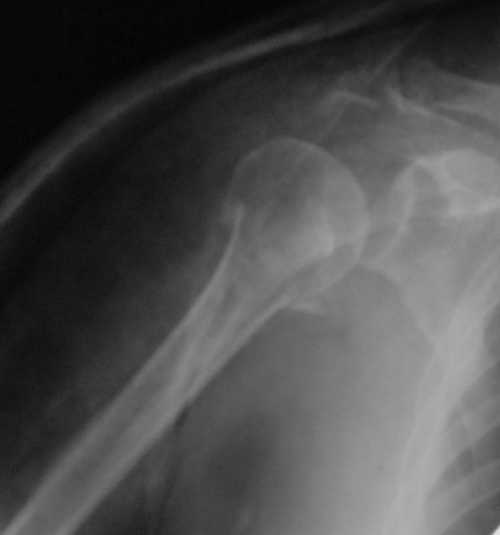

Судя по Р-граммам имеется оскольчатый перелом головки плеча. Во время открытой репозиции имеется большой риск "развалить" перелом, что значительно ухудшит кровоснабжения отломков. А так, на мой взгляд контакт м\у отломками достаточный, не смотря на наличие ротационного смещения головки думаю лучше продолжать консерватикное лечение. С уважением.

Судя по снимкам еще имеется перелом головки плеча, и чрезкостный отрыв вращательной манжеты. Для уточнения характера перелома не иешало бы сделать КТ. Если вести консервативно, то после сращения перелома будет ограничение движений в суставе не устраивающее больную. Я склоняюсь к оперативному лечению( накостный остеосинтез Т- Г образная пластина, лучше LCP для проксимальног плеча, обязательно подшить на место манжету).

В соответствии с работами Neer данный перелом можно классифицировать как однофрагментарный, так как нет диастаза более 1 см и углового смещения более 45 градусов - такие переломы лечатся консервативно. Рентген контроль каждые 10 дней- если смещение не увеличивается, то через 3-4 недели разработка движений в суставе

Уважаемый Сергей! Вы правильно написали критерии, но недооценили степень смещения в переломе хирургической шейки. Посмотрите ещё раз, это Two part fracture.